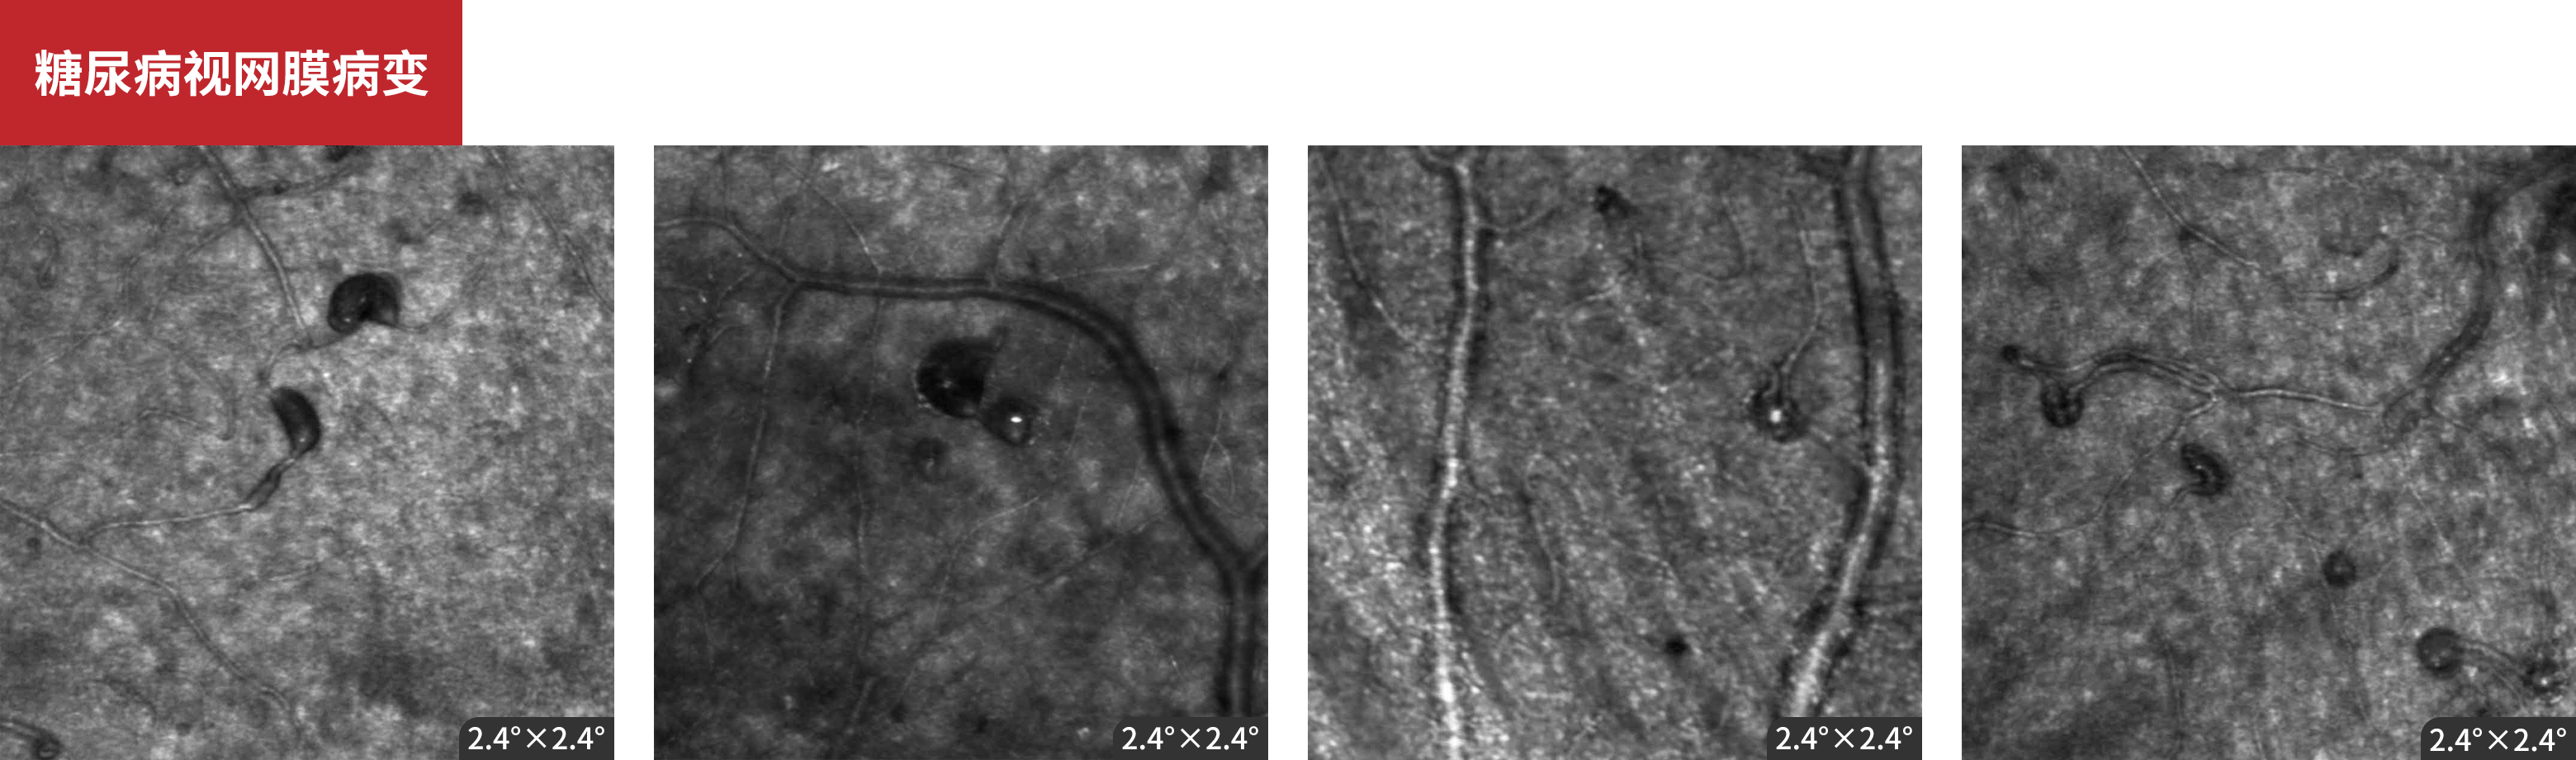

糖尿病视网膜病变